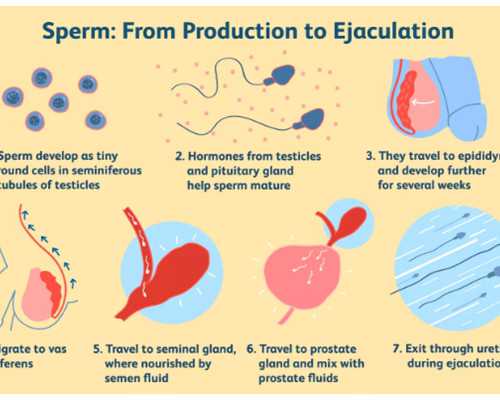

供卵服務的基礎費用通常包括一系列醫療檢查項目,如激素水平檢測、超聲監測和遺傳篩查等,這些檢查確保供體健康和安全。藥物費用占比較大,涉及促排卵藥物的使用,其價格受品牌和劑量影響,波動在數千元到上萬元不等。在公立醫院,這類費用相對規范,常納入醫保部分報銷范圍;而私立機構可能提供更靈活的選項,但需自費承擔。家庭在選擇時,應要求機構提供明細清單,避免隱性收費。